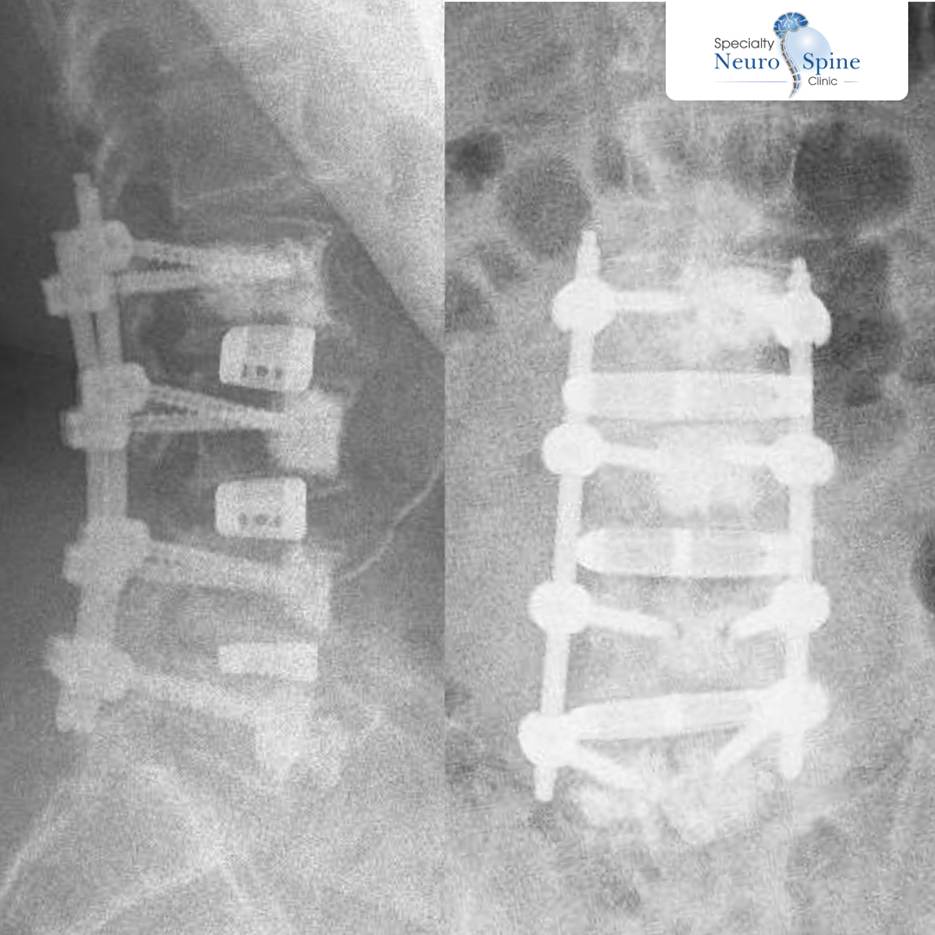

The X-Ray image above shows a part of 81-years-old) Mohammad Al-Shammari’s spine from the back and side after undergoing the OLIF procedure – (Source: Dr. Firas Husban / Checkers Inc.)

Dr. Husban performed a minimally invasive endoscopic procedure to stabilize vertebrae L2 through L5. The surgery was completed through small skin incisions with no bleeding or complications – a testament to the safety profile of this advanced technique.